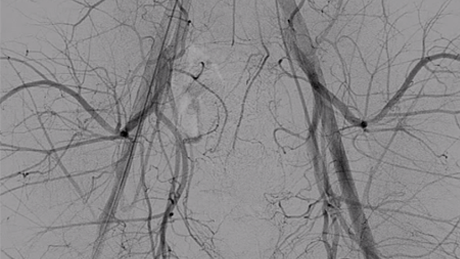

Direxion™

and Direxion HI-FLO™ Torqueable Microcatheters

View More Cases Of Use With The Direxion Torqueable Microcatheter